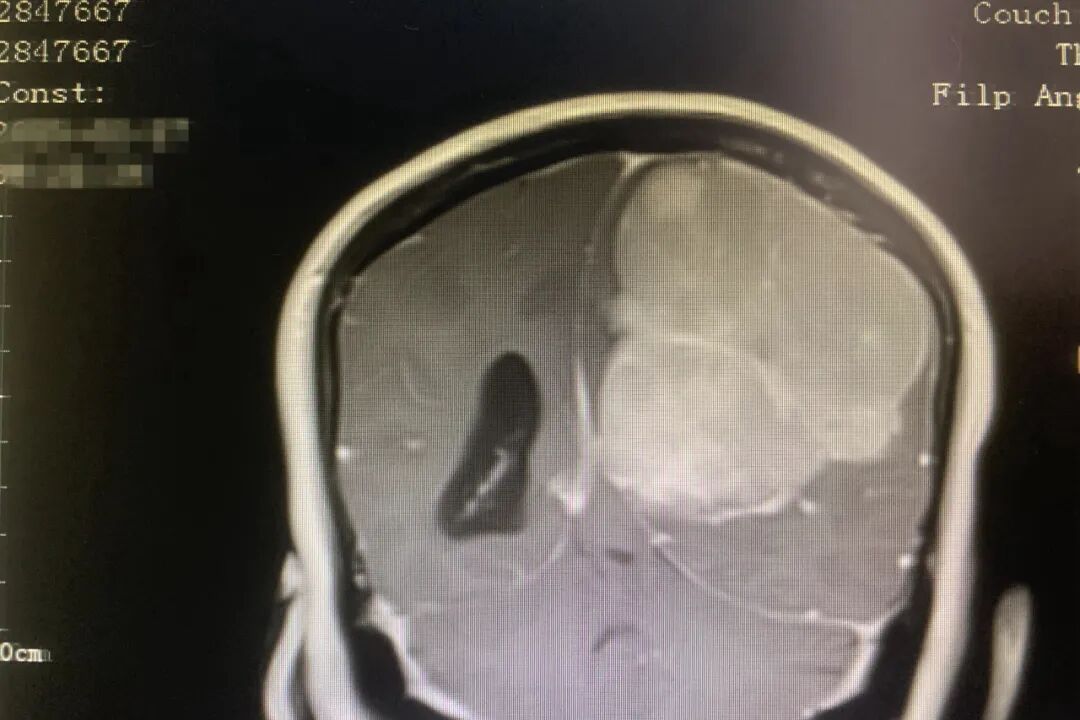

日前,廉江市人民医院神经外科团队经过近10小时的奋战,成功为一名56岁合并多重基础疾病的女性患者实施高难度颅内肿瘤切除手术。切除的肿瘤体积堪比成人拳头(直径达72mm)。

患者李女士因右侧肢体乏力、行动迟缓、言语混乱等症状就医,经检查诊断为左侧额顶部直径巨大脑膜瘤(直径72mm),肿瘤已侵袭运动、感觉功能区及深部重要血管神经,若不及时治疗将危及生命。同时该患者入院后检查发现有高脂血症、甲状腺功能减退、高尿酸血症等基础疾病,手术风险较高。面对极高风险,在医务科的协调下,神经外科邀请了脑卒中·烧伤科、内分泌·老年病科、放射科等科室开展多学科会诊,制定周密手术方案及应急预案。

手术采用“左侧额颞顶部开颅显微镜下脑膜瘤切除术”,术中,麻醉团队精准调控生命体征,放射科实时提供影像支持,血库待命保障用血,多学科无缝衔接为手术护航。从患者入室准备到到手术结束历时近10小时,神经外科团队成功完成手术。医生攻克了三大技术难点:精准剥离体积达6.6×7.2×6.9cm巨瘤;保护了受侵运动、感觉功能区,深部结构,规避重要血管神经。手术成功突破传统局限,在复杂颅脑手术中实现了功能区肿瘤全切与神经功能保全。术后次日,患者即恢复清醒,肢体活动能力显著改善,住院16天后康复出院。